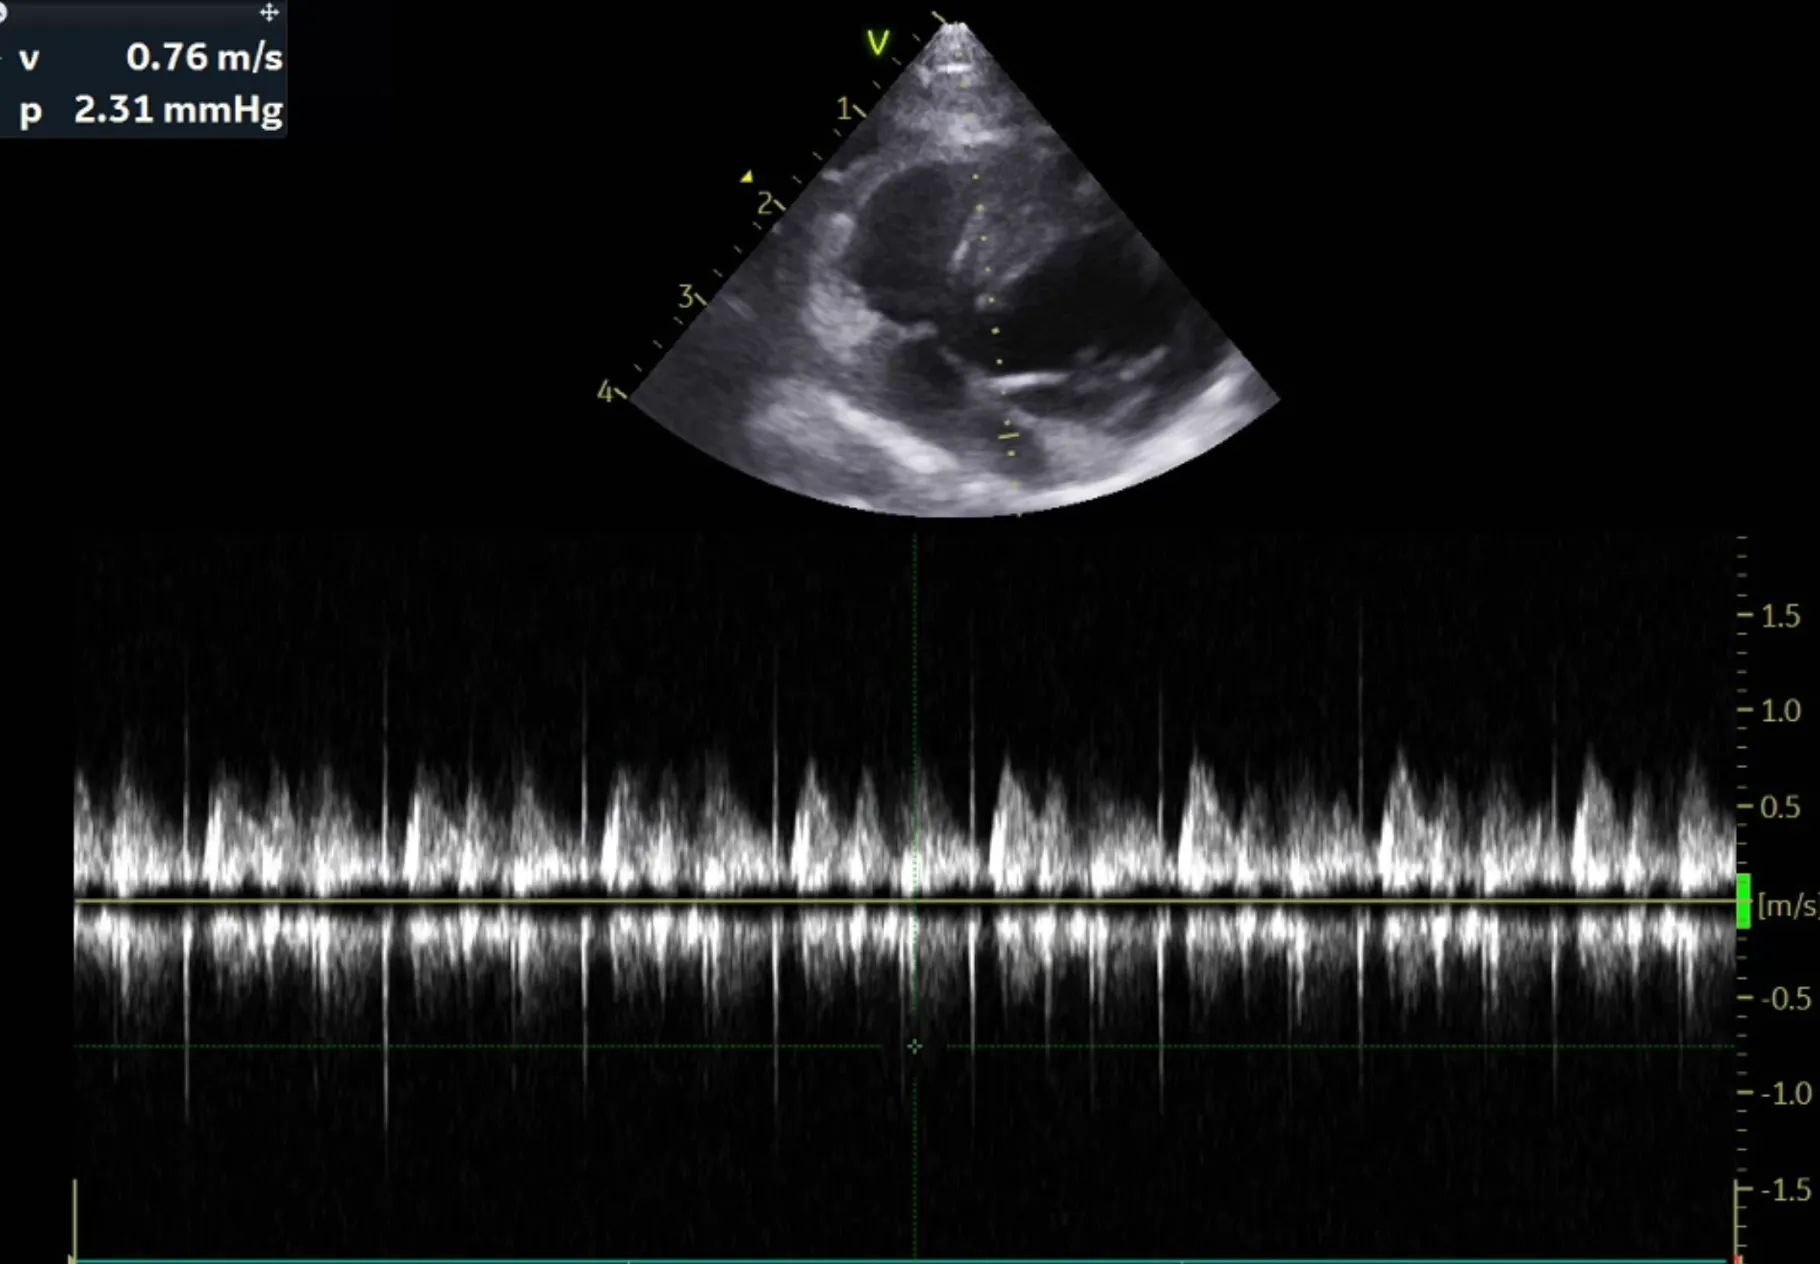

2. 심장 초음파 검사 결과

곰이 의 심장초음파 영상전공의 소견은 다음과 같습니다.

RPS short axis heart base view

LA/Ao ratio 1.47로 정상범위(0.88-1.7), 유의미한 LA 확장 없음

분류 수치

IVSd 4.66/4.58(2.80 - 4.90㎜) - 정상/정상

LVIDd 15.83/15.17(12.20 - 19.20㎜) - 정상/정상

LVPWd 4.21/4.09(2.80 - 4.80㎜) - 정상/정상

IVSs 6.06/5.17(4.30 - 8.40㎜) - 정상/정상

LVIDs 11.20/10.69(5.50 - 12.60㎜) - 정상/정상

LVPWs 4.66/5.02(4.60 - 8.50㎜) - 정상/정상

EF 59.9%/60.5%(40% - 67%) - 정상/정상

FS 29.3%/29.5%(30% - 49%) - 감소/감소

LVIDDN 0.98

EDVI 23(~100)

ESVI 9(~30)

Echo_comments

HCM으로 의심될만한 소견 관찰되지 않음

주치의 소견은 다음과 같습니다.

곰이 는 심장 초음파 검사 결과 현재 심잠벽의 두께는 정상이며 수축기능, 이완기능(심장이 정상적으로 잘 뛰는 것을 확인하는 검사) 모두 정상입니다.

심장 초음파는 1년에 한번씩 검사 받는 것을 추천드립니다.